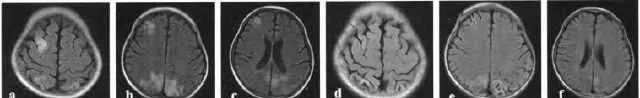

头部 MRl T2 Flare像:a-c是移植前;d-f是移植后8个月